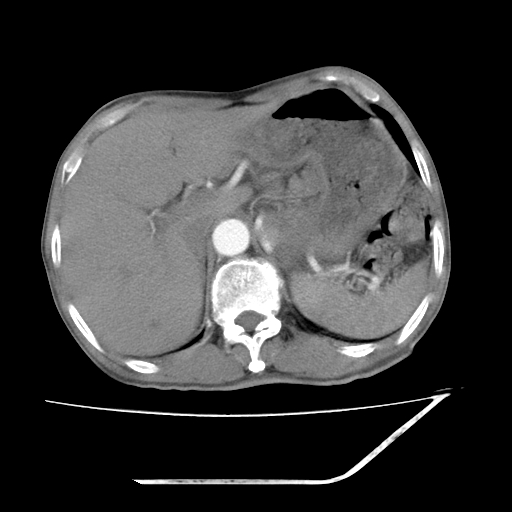

平扫

考虑右肾盂癌,肾动脉受侵,右肾功能减退,右肾盂输尿管积水,管壁增厚,考虑种植转移,应该把下面扫完的

支持右侧肾盂癌伴肾静脉瘤栓形成可能性大,右肾结石.肝右叶后段低密度影,不除外转移.

右肾盂旁ca并肾静脉瘤栓形成/肾功能降低。

右肾结石。

右肾盂癌,肾动脉受侵,右肾盂输尿管积水,管壁增厚,考虑种植转移

支持 右侧肾盂癌伴肾静脉瘤栓形成可能性大,右肾结石;肝右叶后段低密度影,不除外转移。

1.右侧肾盂癌伴肾盂积水。

2.肾脏功能减退,原因有:(1)肾动脉受侵。(2)肾静脉受侵(3)肾积水,等。本例,肾动脉显影较好,但受压明显;肾静脉无明显显示,受压或静脉癌栓,下腔静脉腔内未见明显充盈缺损。

3.右侧上段输尿管扩张,原因:(1)积水所致;(2)种植。